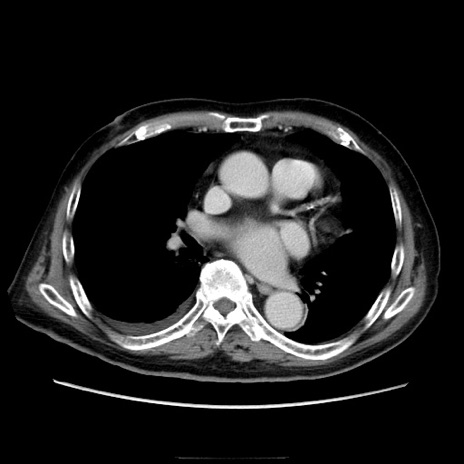

症例21(横断像)

【症例】70歳代男性

【主訴】腹痛

【現病歴】肝硬変・肝細胞癌にてかかりつけの方。約9時間前に食後より腹痛出現。症状が徐々に増悪し、嘔吐出現したため来院。

【既往歴】肝硬変、肝細胞癌(RFA、TACE後)

【身体所見】意識清明、表情苦悶様、BT 36℃、BP 129/78mmHg、P 88bpm、SpO2 97%(RA)、右上腹部から心窩部にかけて圧痛あり、反跳痛なし、筋性防御あり。

【データ】WBC 5800、CRP 0.16